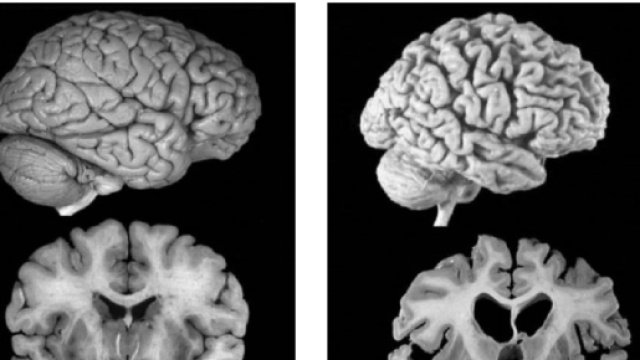

La seconda ricerca si è concentrata sui livelli di NfL (catena leggera del neurofilamento) nel liquido cerebrospinale e nel siero, correlati tra loro. Nelle fasi precoci della malattia (fase pre-sintomatica), i livelli di NfL iniziano ad innalzarsi e questo è predittivo del tasso di assottigliamento corticale che si traduce in una riduzione delle capacità cognitive. Seguendo questi pazienti nel tempo, dopo qualche anno si manifestano tutti i sintomi dell'Alzheimer, confermati dalla risonanza magnetica e dalle placche di β-amiloide. NfL è quindi un utile biomarcatore rilevabile nel plasma, clinicamente sfruttabile per arrivare ad una diagnosi precoce di Alzheimer.

È la presenza di due proteine che caratterizzano l'Alzheimer, la β-amilode e la proteina tau.